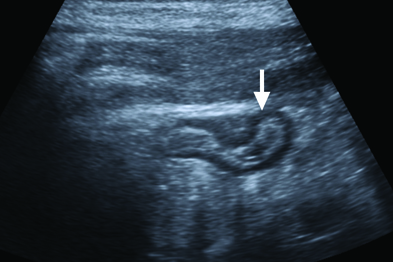

Appendicitis treatment usually involves surgery to remove the inflamed appendix Before surgery you may be given a dose of antibiotics to treat infection Surgery to remove the appendix (appendectomy). The Alvarado score, Pediatric Appendicitis Score, and Appendicitis Inflammatory Response score incorporate common clinical and laboratory findings to stratify patients as low, moderate, or high risk and can help in making a timely diagnosis Recommended firstline imaging consists of pointofcare or formal ultrasonography. Doctors typically treat appendicitis with surgery to remove the appendix Surgeons perform the surgery in a hospital with general anesthesia Your doctor will recommend surgery if you have continuous abdominal pain and fever, or signs of a burst appendix and.

BolakaleRufai IK(1), Irabor DO(1) Author information (1)Department of Surgery, University College Hospital, Ibadan, OyoState, Nigeria Appendicectomy has been accepted as the gold standard for the management of appendicitis over the years, but there has been an increasing. If investigation is required, computed tomography scan or ultrasonography may show dilatation of the appendix outer diameter to more than 6 mm Definitive treatment is surgical appendectomy A nonoperative, antibioticonly approach may be feasible in select patient populations. Similar to in the nonpregnant population, medical management of ruptured appendicitis in pregnancy may be a reasonable treatment option Similar to the nonpregnant population, medical management of ruptured appendicitis in pregnancy may be a reasonable treatment option © 09 by The American College of Obstetricians and Gynecologists.